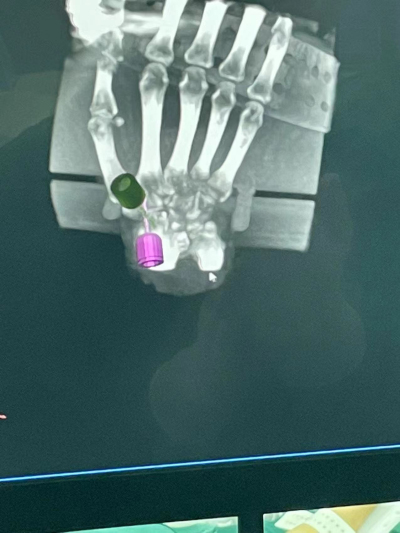

近日,手足显微外科中心郝增涛教授团队再次完成一例“天玑Ⅱ”骨科手术机器人导航下精准定位经皮内固定舟骨骨折桡骨远端骨折,在机器人的帮助下做到了置钉角度和位置最佳,既缩短了手术时间,又减小患者创口,同时又缩短了医生在X线下操作的时间,最大程度地保护了医生和患者。

据郝增涛主任介绍,由于腕舟骨体积小、解剖结构复杂,螺钉置入位置欠佳,会引起骨折处稳定性不良,还有愈合时间长。而有了骨科手术机器人参与手术,精准导航,螺钉可一次性成功置入,减轻了手术风险,使患者受益良多。“天玑Ⅱ”骨科手术机器人可谓是一个好帮手、好伙伴。